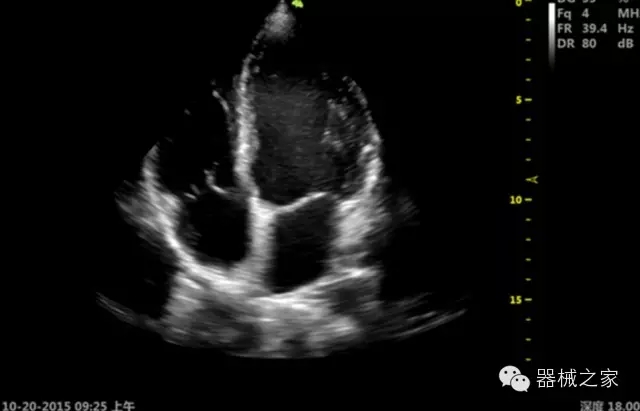

·心功能綜合指數(shù)(TEI指數(shù)):用于左、右心室整體心臟收縮舒張功能評估的測量方法;

·全方位可調(diào)M型:有利于更好的觀察心腔大小及室壁階段性運動的異常情況;

·組織多普勒成像(TDI):TDI可定量評價心肌運動,判斷是否有局部病變,還可評價早期的舒張功能;